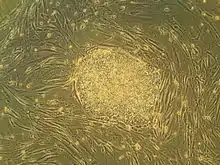

Stem cells

Stem cells are cells that can differentiate to become different types of cells.[15] The hope is that stem cells transplanted into an injured area of the spinal cord will allow neuroregeneration.[6] Types of cells being researched for use in SCI include embryonic stem cells, neural stem cells, mesenchymal stem cells, olfactory ensheathing cells, Schwann cells, activated macrophages, and induced pluripotent stem cells.[1] When stem cells are injected in the area of damage in the spinal cord, they secrete neurotrophic factors, and these factors help neurons and blood vessels to grow, thus helping repair the damage.[16][17][18] It is also necessary to recreate an environment in which stem cells will grow.[19]